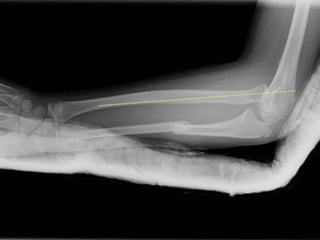

Diagnostic ?

A. Fx olécrâne

B. Fx Cubitus

diaphysaire

C. Monteggia

D. Galleazzi

E. X Wing

Monteggia

Piège Radiologique

• Rx avant bras

• Rx coude